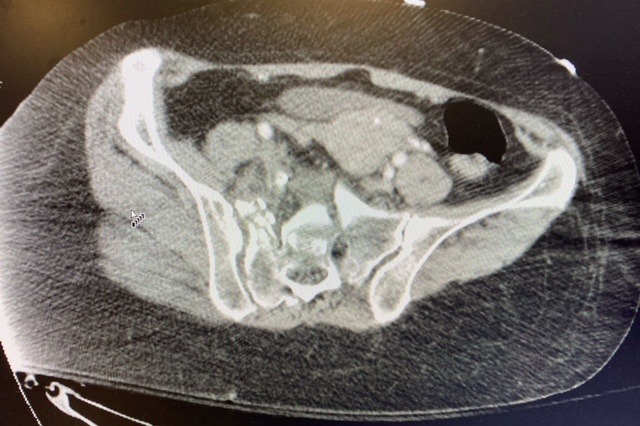

Her injuries are as follows: 1) Broken shoulder blade (Left Side), 2) Ribs 5-11 broken (Left Side), 3)Pneumothorax -needing chest tube (Left Side), 4) Shattered pelvis (see photo), 5) Broken fibula and ankle (Left Side), 6) Fractures to her vertebrae C2, T3, L1 and L5 and concussion.